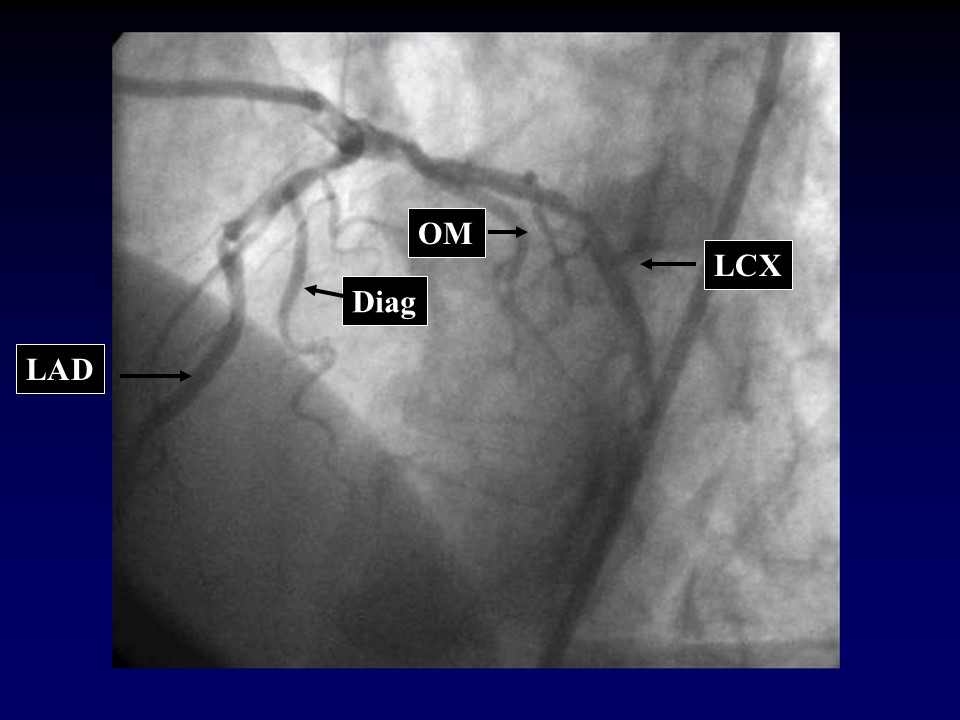

冠脉造影的规范操作PPT